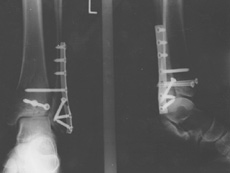

Für die nächsten sechs Wochen sind Rollstuhl und Krücken angesagt...